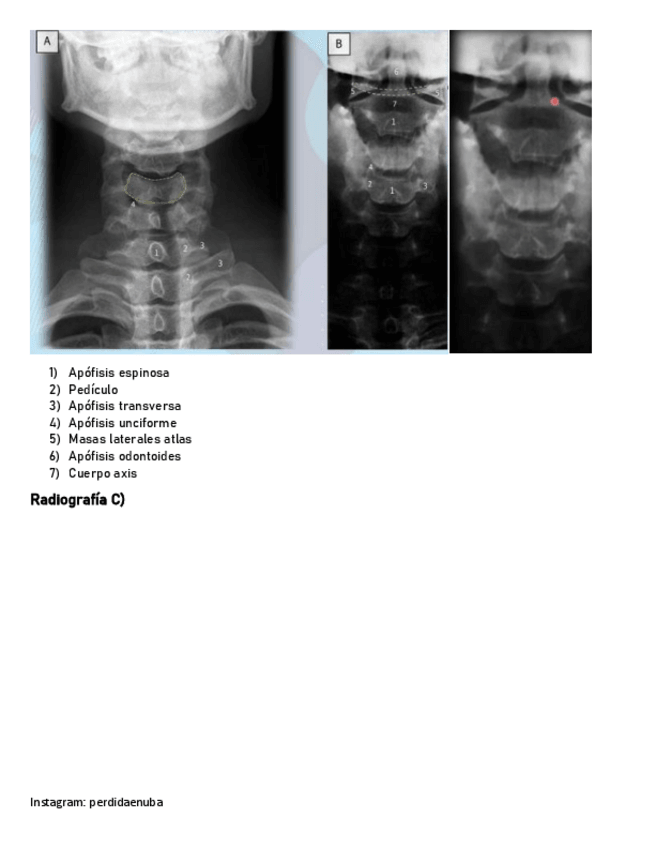

He publicado nuevos apuntes de 8º Cirugía General: MANO-Y-MUNECA.pdf

He publicado nuevos apuntes de 8º Cirugía General: Dorso.pdf

He publicado nuevos apuntes de 8º Cirugía General: CINTURA-PECTORAL-1.pdf

He publicado nuevos apuntes de 8º Cirugía General: BRAZO-CODO-ANTEBRAZO-.pdf